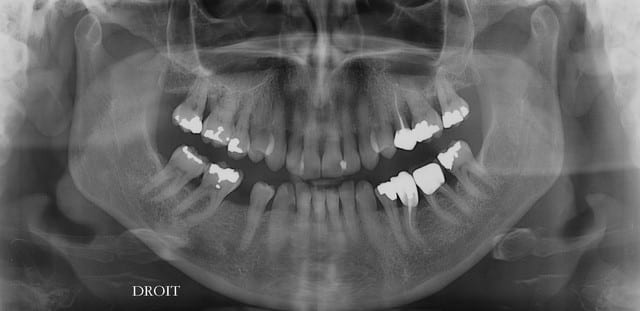

Les panos sont du départ, les photos sont après un nettoyage ...profond et soins.

le problème de départ de cette patiente est paro...et bien sur l'ortho est une bonne idée, mais je ne pense pas que l'ortho permette de rétablir une DV correcte.

Tout à fait d'accord avec le manque de calage par effondrement des spee. Il y a par contre égression du bloc incisif supérieur, d'où surcharge occlusal ne favorisant pas la paro, si on attend trop tout s'écroule. Une réingresser par de l'ortho sur un terrain paro fragile est super long, voir dangereux (aggravation de la paro), le choix de se passer d'ortho ici semble plutôt logique, il est urgent de régler l'occlusion et d’alléger le sur-guidage incisif (le rôle des provisoires molaire mandibulaire).

Mais sur une patient présentant un terrain paro avec lésion infracteuse et lésion de furcation sur certaine zone.

Une reconstruction prothétique n'est elle pas une option plus sage dans les secteur post inférieure ? Pour la maintenance paro et pour mettre des limites sous gingivale.

De plus il me semble que cette patient bruxe légèrement une extrusion post ne risque t'elle pas de récidiver. C'est une des mouvement qui a la moine bonne stabilité dimensionnelle a ma connaissance.

à l'examen des coupes pano, franchement je ne crois pas que ce soit le bon choix.